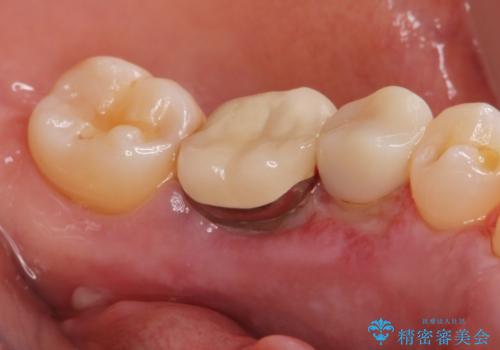

骨隆起除去

- 骨隆起が舌にあたり不快感があるので骨隆起をとりたくて来院。

静脈内鎮静麻酔下で骨隆起を除去を行いました。

骨隆起がなくなり不快感がなくなり大変満足して頂けました。